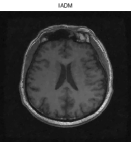

Besides the Shepp-Logan phantom image, we also tested Cameraman, Lena, Boat, Sailboat, as well as two brain images. In this experiment, we simply set and keep all other parameters unchanged. The original and the recovered images by TwIST and IADM are given in Figures 3 and 4, and detailed results including relative errors (RE), CPU time (Time), final objective function values (Obj), and the number of iterations (Iter) are presented in Table 2. It can be seen from Table 2 that IADM attained comparable or better image quality in less CPU seconds. For each test, IADM consumed more iterations while the CPU time is less because the per-iteration cost of IADM is much less than that of TwIST. Specifically, the per-iteration cost of IADM contains two matrix-vector multiplications and two FFTs, while TwIST needs to solve a TV denoising problem at each iteration. In addition, IADM always attained smaller function values. In summary, the comparison results indicate that IAMD performs favorably and can be competitive with the state-of-the-art algorithm TwIST.

| TwIST | IADM | ||||||||

|---|---|---|---|---|---|---|---|---|---|

| Images | Size | Iter | RE | Time | Obj | Iter | Re | Time | Obj |

| brain 1 | 52 | 14.01% | 34.25s | 4.7831e+002 | 208 | 13.64% | 20.41s | 4.5478e+002 | |

| brain 2 | 48 | 9.59% | 90.22s | 1.6397e+003 | 176 | 9.45% | 61.67s | 1.5665e+003 | |

| cameraman | 56 | 5.71% | 122.22s | 2.9068e+003 | 257 | 5.59% | 118.67s | 2.7822e+003 | |

| lena | 53 | 4.93% | 121.06s | 2.3656e+003 | 205 | 5.01% | 92.11s | 2.2627e+003 | |

| man | 59 | 8.54% | 423.38s | 1.0617e+004 | 262 | 8.57% | 400.81s | 1.0122e+004 | |

| sailboat | 57 | 4.91% | 361.58s | 7.9220e+003 | 245 | 4.98% | 260.73s | 7.5960e+003 | |

| sheppon | 42 | 2.62% | 335.36s | 4.4496e+003 | 135 | 2.09% | 217.08s | 4.2317e+003 | |

| boat | 53 | 4.37% | 477.17s | 8.7306e+003 | 200 | 4.34% | 384.61s | 8.3312e+003 | |

| barbara | 56 | 9.83% | 493.20s | 1.3469e+004 | 292 | 9.80% | 550.39s | 1.2814e+004 | |